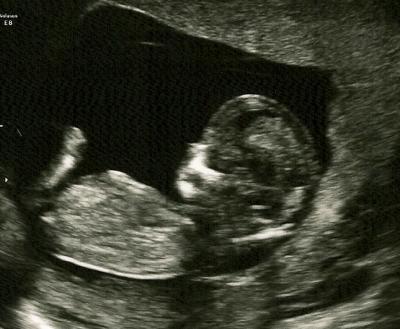

Heute Nackenfaltenmessung ! :-) Alles in bester Ordnung! die Statistik sagte 1:179 nach der Untersuchung war es dann 1: 3998 :-) ♥ bin total HAPPY! Die Ärztin sagte: Einen Befund wie bei einer 15 jährigen.... ^^ :-D

Bild zu Bildchen von NF-Messung :-) Alles gut!!! - Forum für August - Mamis

Hallöchen, Glückwunsch zu dem tollen Ergebnis! Ein wundervolles Bildchen hast Du von Deinem Krümel bekommen! :-)) Wünsche Dir noch einen schönen Abend! Lg Mone

Schön, dass alles in Ordnung war und ein sehr süßes Bildchen!!

herzlichen Glückwunsch zum tollen und beruhigenden Ergebnis... Ich habe morgen meinen Termin für die Nt-messung und bin ehrlich gesagt ziemlich aufgeregt. Aber da ich schon 4 gesunde KIDS geboren habe , gehe ich davon aus , das es auch diesmal gut gehen wird. das Bild ist wirklich schön getroffen.. lg und weiterhin eine schöne Schwangerschaft...